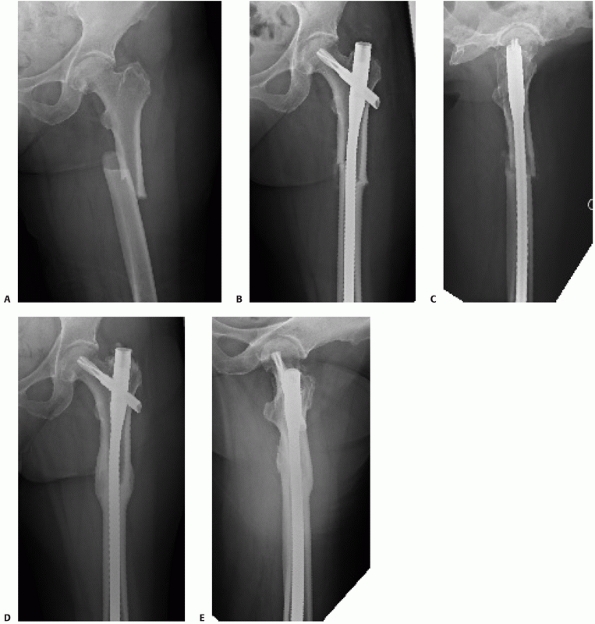

based largely on the fracture morphology and includes the fracture

location as well as the degree and type of comminution (Fig. 50-3).

Type A fractures are considered simple and include spiral, oblique, and

transverse patterns. Type B fractures are wedge fractures and include

spiral wedge, bending wedge, and segmental wedge patterns. Type C

fractures are considered complex patterns that have no predicted

cortical contact between the major proximal and distal fractures. These

fractures are divided on the basis of the same characteristics

described for B fractures. Each of these fractures is further divided

on the basis of location as subtrochanteric, middle, or distal.

Although the precise alphanumeric classification assigned to each

femoral fracture is of limited utility, an understanding of the

fracture pattern and its location assists with surgical planning and

may be useful for documenting and categorizing large numbers of femoral

fractures.

![]() |

FIGURE 50-3

Association for the Study of Internal Fixation classification of fractures of the shaft of the femur. Simple fractures (type A) are distinguished by the degree of obliquity of the fracture line. Wedge fractures (type B) are subclassified according to the anatomy of the wedge fracture. Complex fractures (type C) can be spiral, segmental, or irregular. |